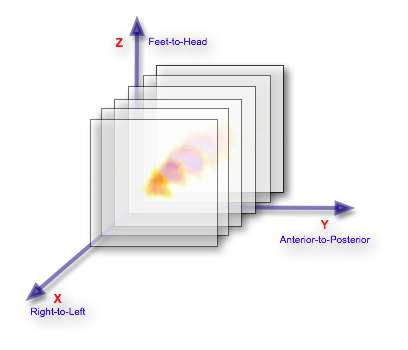

Its helpful, before proceeding, to consider the axial slices, be they SPECT or CT, stacked one behind the other, as illustrated below:

Notice that the figure illustrates each image as a thin slice when the data represents in reality a slice wide enough to fill the gap between it and the next slice, so that the image data can be considered to be a matrix of volume elements - called voxels for short.

A convention applied in medical imaging is to display axial image stacks with the axes oriented as shown in the following figure: